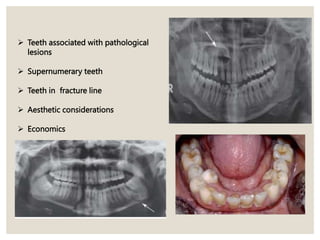

 Teeth associated with pathological

lesions

 Supernumerary teeth

 Teeth in fracture line

 Aesthetic considerations

 Economics